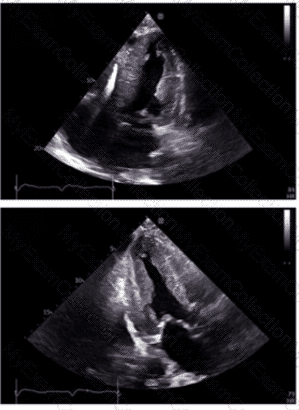

Which diagnosis is most likely confirmed by echocardiography in a 65-year-old female presenting with new onset chest pain associated with ST segment elevation on the electrocardiogram and angiographically normal coronary artenes?